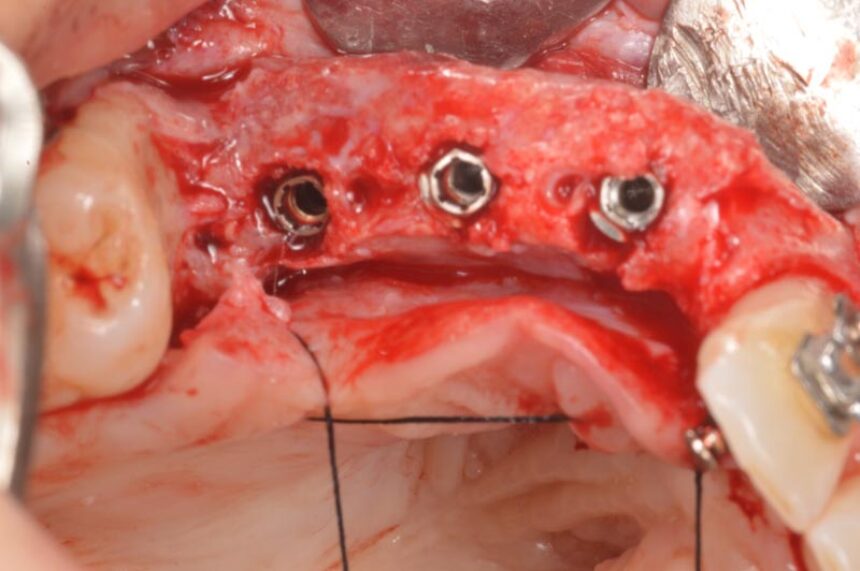

The totally edentulous mandible: different atrophies and corresponding surgical techniques - Short implants - Bone grafts – GBR

Horizontal and Vertical Ridge Augmentation: scientific background - surgical techniques – resorbable and non-resorbable membranes - bone graft harvesting from intra-oral sites – video

Surgical techniques for hard and soft tissue augmentation.